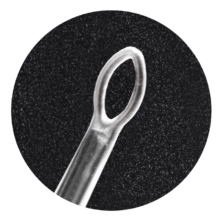

Texa Biomedicali seleziona i migliori prodotti nell’ambito del Monouso per Otorinolaringoiatra (ORL). Alta affidabilità e standard qualitativi in relazione alla vendita di Kit ORL sterili, curettes ORL, speculum monouso.